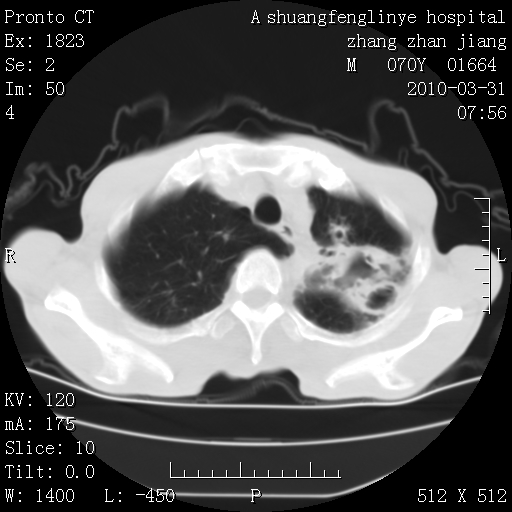

双上肺继发型tb并左上空洞形成,主动脉冠脉钙化。

支持:继发性肺结核伴空洞形成!建议纤支镜检查待出外周围型肺癌可能!

1)两肺上叶继发性肺结核并左肺上叶空洞形成。2)冠状动脉及主动脉钙化。